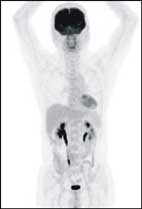

● 正常氟-18去氧葡萄糖生理分佈

PET/CT為結合正子掃描與電腦斷層的複合式掃描儀,除了用去氧葡萄糖來偵測體內高代謝腫瘤病灶的正子功能顯像外,更加上了電腦斷層掃描來精確結構定位。這兩種影像檢查各有擅場,互補後大幅提高診斷的準確與精確性。正子電腦斷層造影兼具安全無痛、大範圍全身檢查的優點,是近年來相當重要的醫學發明。